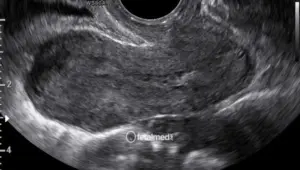

A biópsia de vilo corial (BVC) é um procedimento invasivo para diagnóstico genético precoce, realizado no primeiro trimestre da gestação. Consiste na coleta de uma pequena amostra de tecido placentário (vilosidades coriônicas) que possui o mesmo material genético do feto.

Guiada por ultrassom, uma agulha é introduzida através do abdômen materno até a placenta. Uma pequena amostra de tecido é aspirada. O procedimento dura poucos minutos e é realizado em ambulatório.